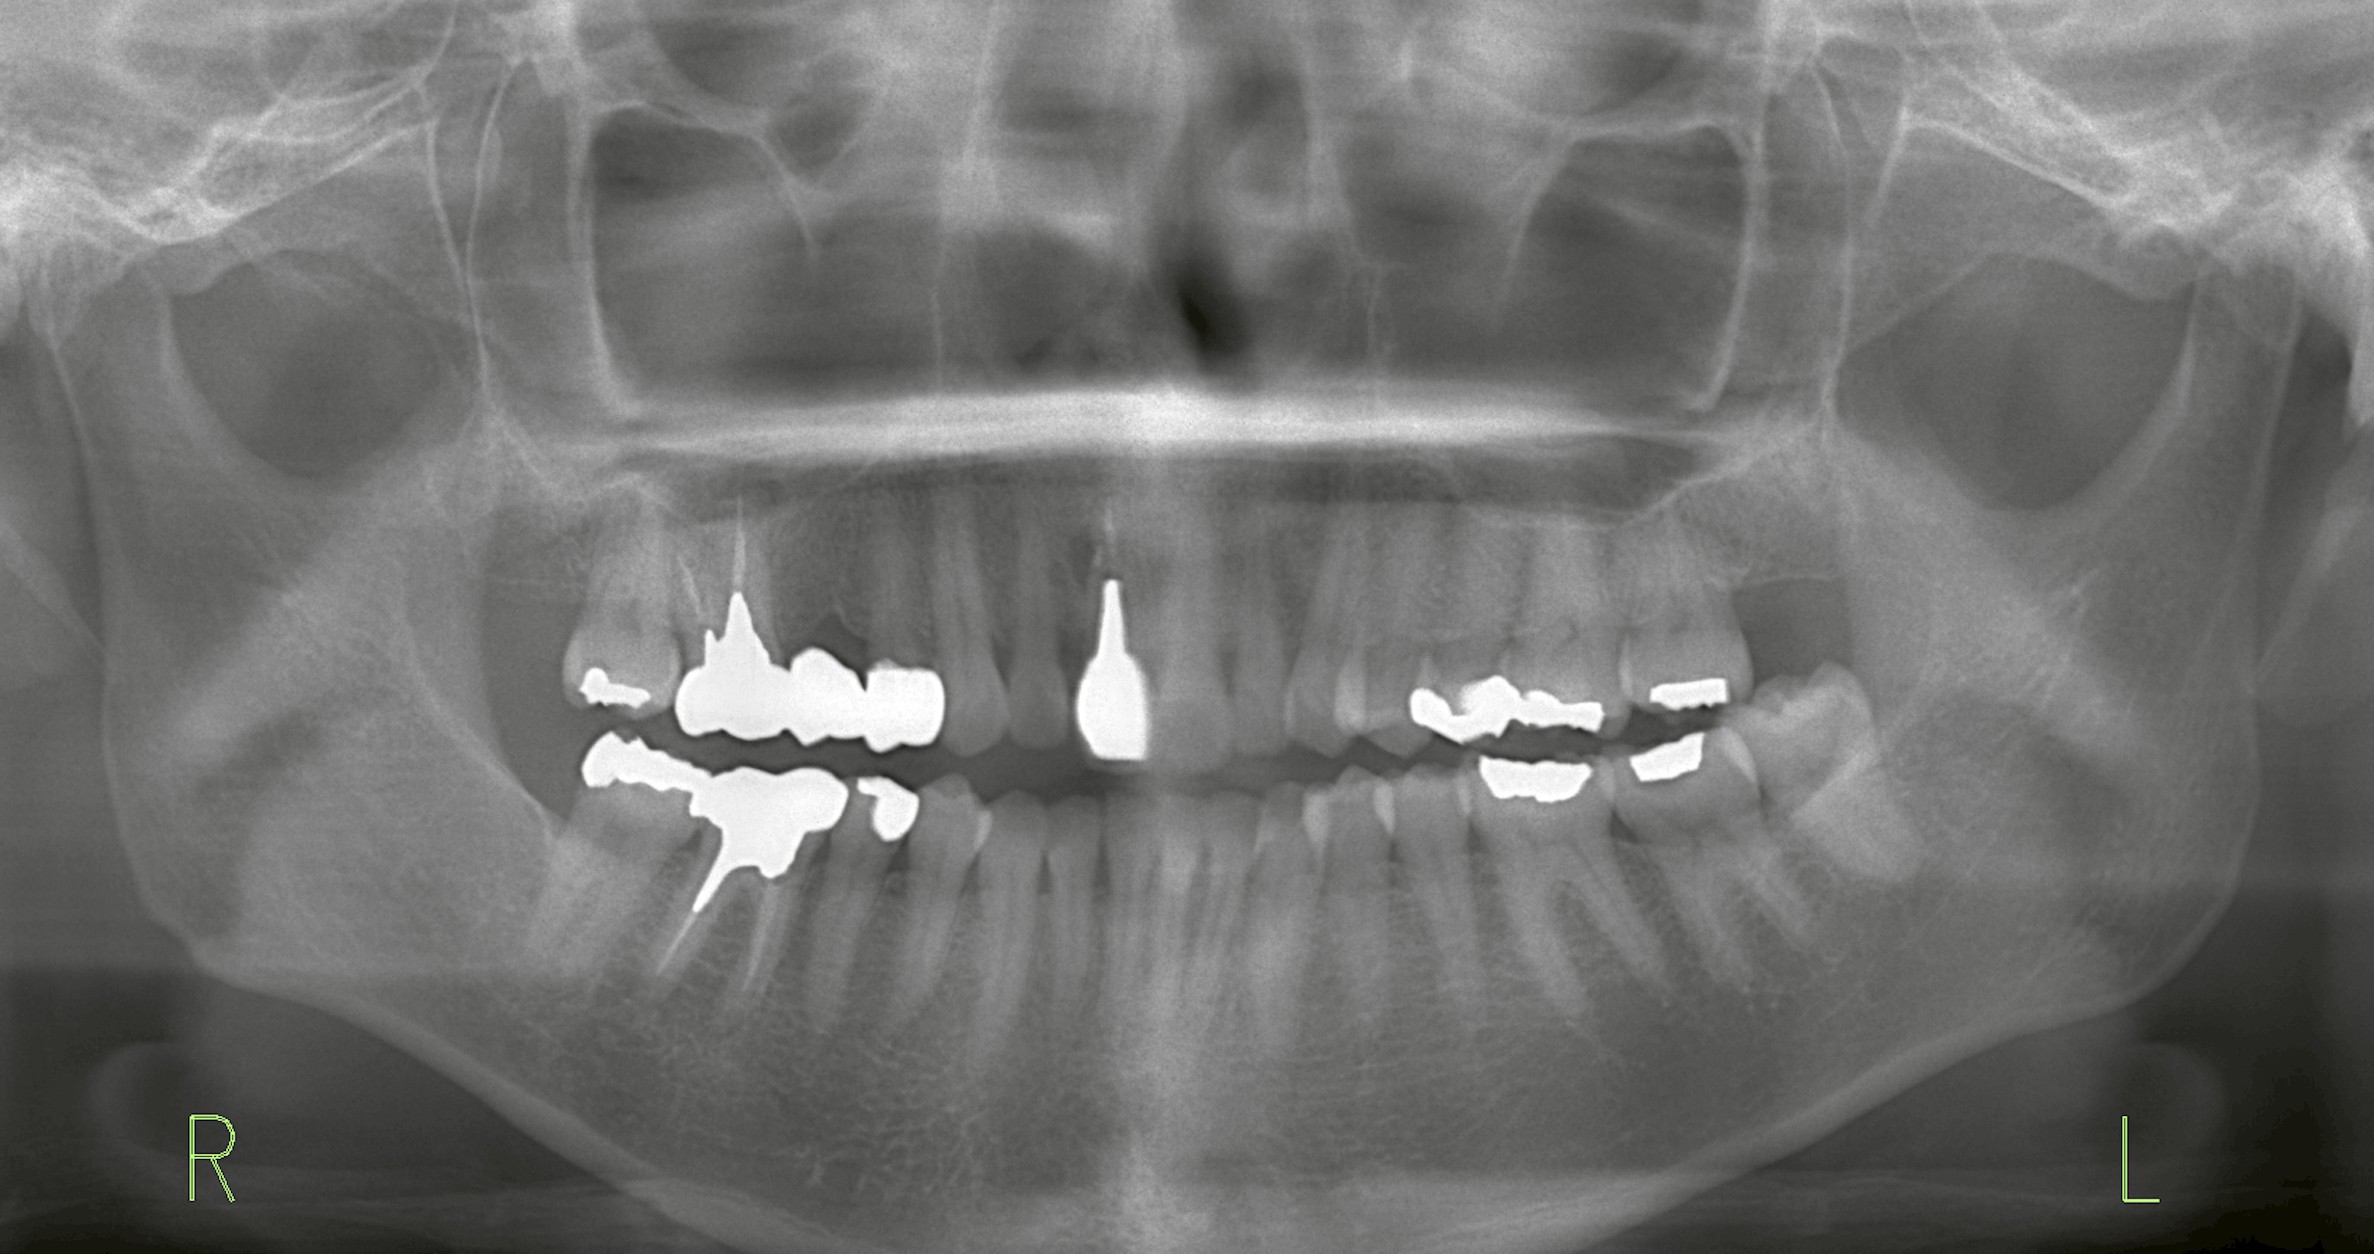

抜歯が必要な状態に

前歯は見た目の印象を大きく左右するため、保存を最優先に考えます。しかし今回のケースでは、歯根の状態が悪く、抜歯が避けられない状況でした。

インプラントは確かに優れた治療法ですが、今回のケースでは問題がありました。

抜歯部位の骨欠損が大きく、骨造成(骨を補う手術)が必要だったのです。さらに、両隣の歯肉の高さや審美性を考慮すると、1回の手術だけでは難しく、複数回に分けて治療が必要になる可能性がありました。